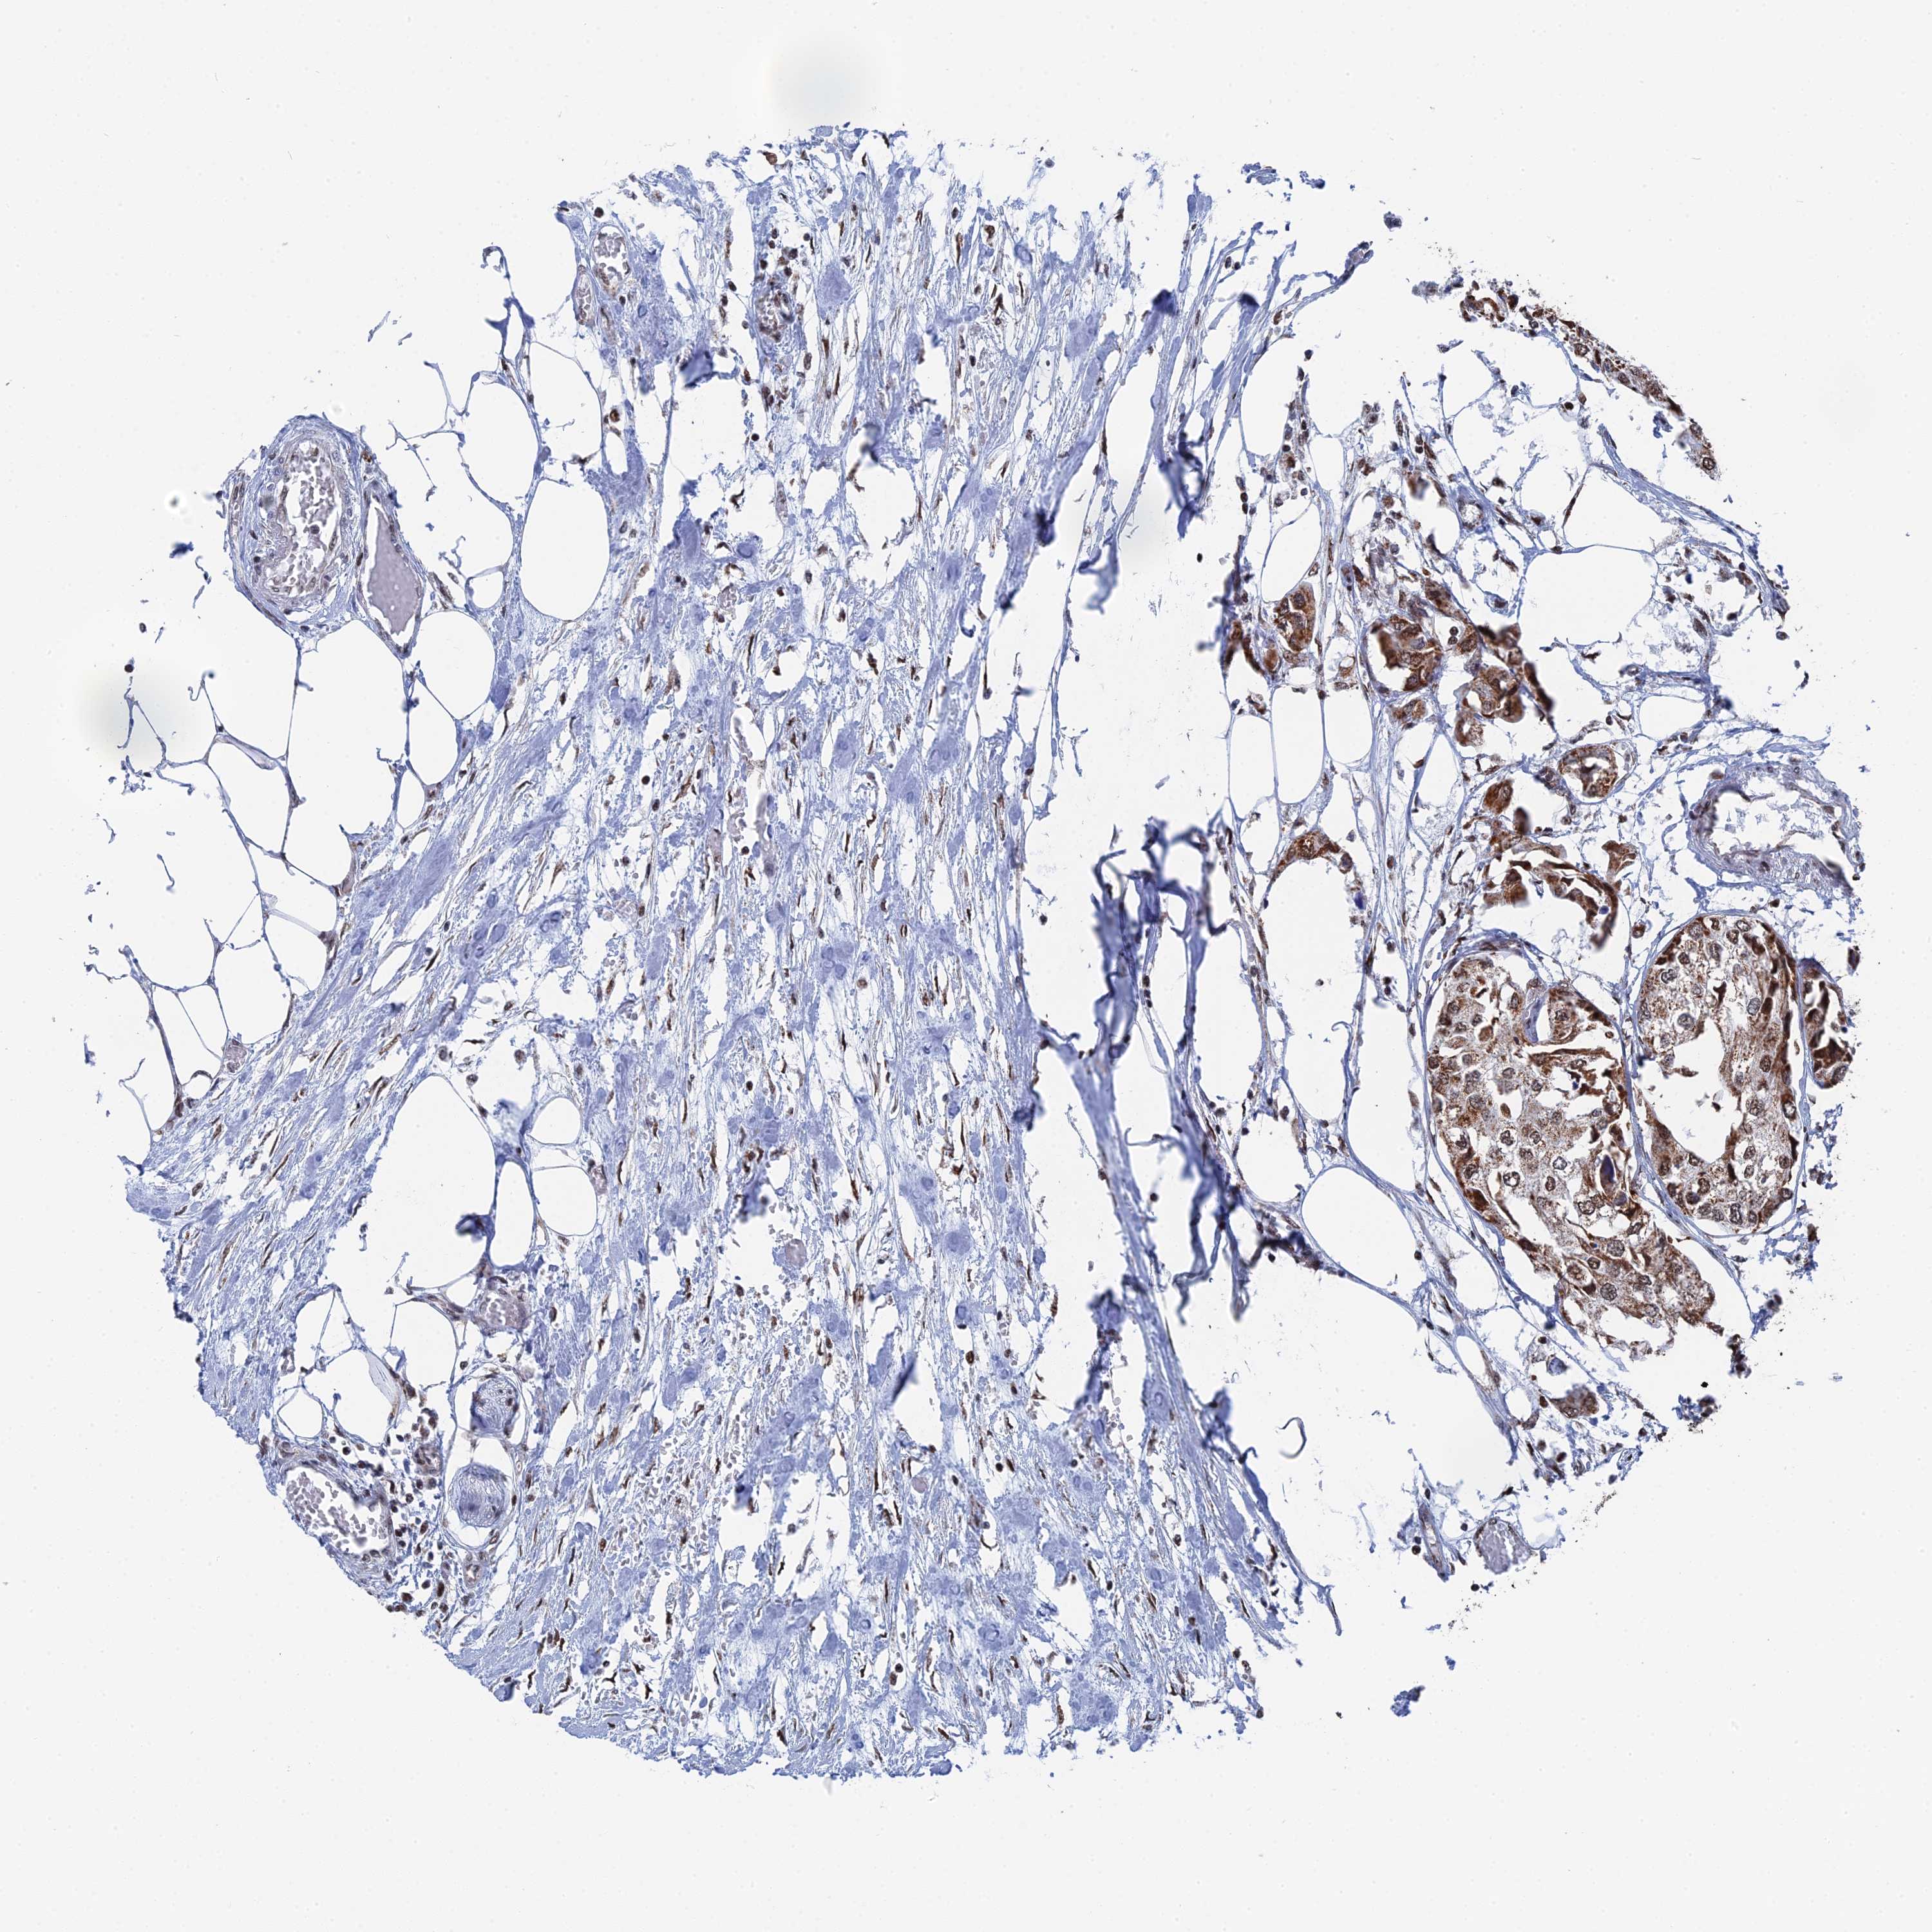

UROTHELIAL CANCER - Protein expressioni

A mouse-over function shows sample information and annotation data. Click on an image to view it in a full screen mode. Samples can be filtered based on level of antibody staining by selecting one or several of the following categories: high, medium, low and not detected. The assay and annotation is described here.

Note that samples used for immunohistochemistry by the Human Protein Atlas do not correspond to samples in the TCGA dataset.

Antibody stainingi

Antibody staining in the annotated cell types in the current human tissue is reported as not detected, low, medium, or high, based on conventional immunohistochemistry profiling in selected tissues. This score is based on the combination of the staining intensity and fraction of stained cells.

Each image is clickable and will lead to virtual microscopy that enables deeper exploration of all samples and also displays staining intensity scores, fraction scores and subcellular localization as well as patient and tissue information for each sample.

Antibody HPA042559

Antibody HPA044208

Staining

High

Medium

Low

Not detected

Intensity

Strong

Moderate

Weak

Negative

Quantity

>75%

75%-25%

<25%

None

Location

Nuclear

Cytoplasmic/membranous

Cytoplasmic/membranous,nuclear

Urothelial carcinoma, High grade